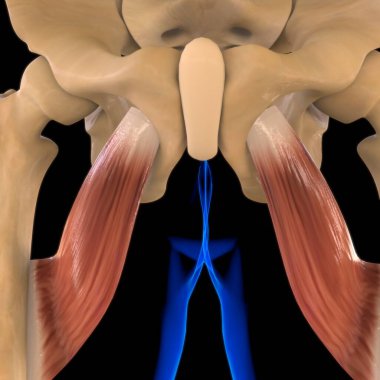

Tıbbi konsept 3 boyutlu illüstrasyon için insan kadın kas anatomisi

KasBileşenlerDorsalfleksörPalmarbrachiiBrevisLongusabdüktöradductorekstansiyonOrasına3d oluşturma3B illüstrasyonCarpiteresdeltoideusDigitorumbrachioradialiskomplikasyondigitiquintipollicisprofundusulnarispronatorPalmarisinterosseiopponenscoracobrachialisKas Anatomisilongus muscleinterossei musclebrevis musclelummbrical muscletricep mucslepollicis musclesuperficialis muscleBenzer İçerikler